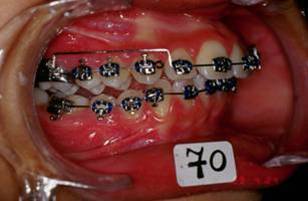

Merci pour tous ces messages qui montrent que vous estes tous sensibles a cette retrogenie, et surtout votre concepte anti-extraction. Figurez vous et c'etait exactement mon point de vu de depart car j'ai pris ce cas comme un type caucasien, europeen et j'ai fait le deverrouillage necessaire sous toutes ses formes mais la mandibule n'a pas voulu avancer du tout, meme pas un mm!! Je crois que la typologie ethnique, sagittal et vertical, de cette patiente ne permettait pas l'avancement mandibulaire par contre l'avancement alveolaire, bonjour les degats!!!!! Une autre difference, dans un pays chaud une fille de 12 ans c'est comme une fille de 14 ans dans un pays froid, il ne faut pas fantasmer sur ce que je dits mais c'est la verite?!!

Voici les photos intermediaire apres: un QH, reeducation,propuleur Balters simple, multi-bague avec el II ancrage maxi bas, mini haut avec le trace. La maman et la patiente n'etaient pas d'accord du tout! Je comprends tout a fait leur point de vue... A suivre

Picture1 pvviml - Eugenol

Picture2 ghm9hp - Eugenol

Picture3 yvnauf - Eugenol

Picture4 pk0wos - Eugenol